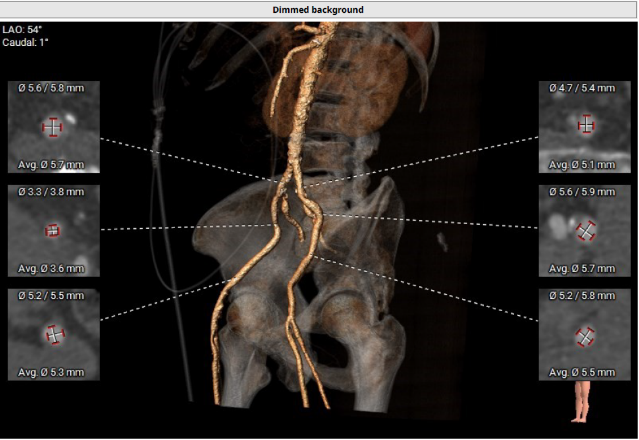

外周血管评估

经过医院多学科团队术前测量对病例深入分析,同时结合AI术前分析辅助决策软件进行三维和二维图像融合结果,指出本例难点/要点主要包括:

• 外周血管入路最狭窄处直径无法满足经动脉TAVR手术器械的输送要求。

• 全麻下经心尖入路,植入Xcor™-23经导管主动脉瓣膜。使用较小球囊(18mm)预扩病变,同时再次评估/确认钙化情况及人工瓣膜尺寸选择合理性。